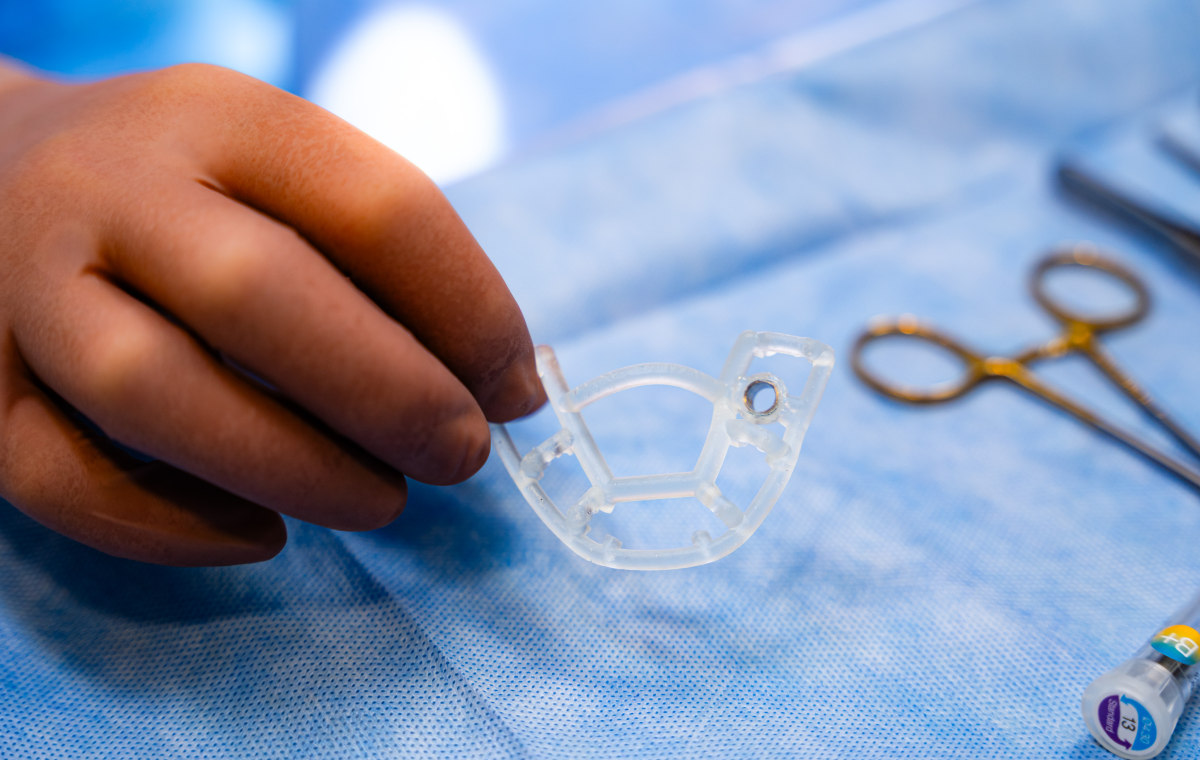

Chirurgie implantaire guidée avec guide 3D

La chirurgie implantaire guidée consiste à planifier l’intervention de manière entièrement numérique avant même de toucher à la bouche du patient. À partir d’un scanner 3D et d’empreintes numériques, nous concevons virtuellement la position idéale de l’implant, puis nous fabriquons un guide chirurgical imprimé en 3D, parfaitement adapté à votre anatomie. Ce guide permet une pose d’implant extrêmement précise, plus rapide, plus confortable et plus sécurisée, en respectant au millimètre les structures anatomiques.